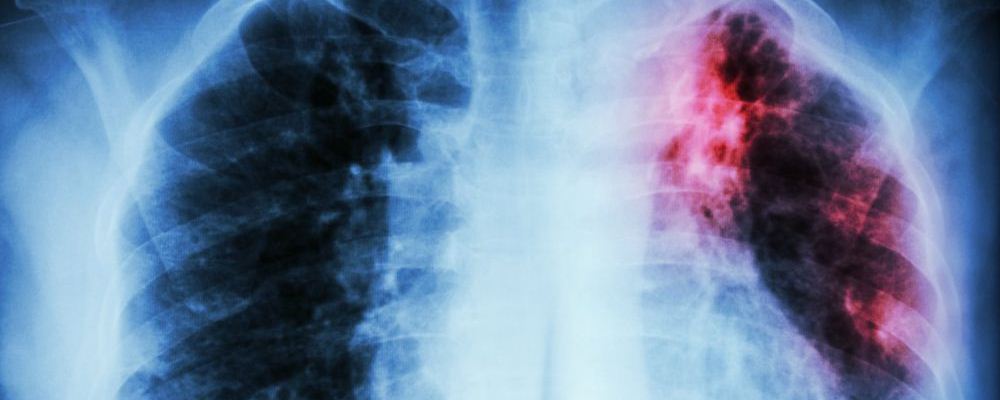

肺癌可是很可怕的疾病,其發(fā)病率和死亡率都很高,是一種威脅人的健康和生命的惡性腫瘤。早期發(fā)現(xiàn)問題治療恢復(fù)的可能性比較大,可是到了肺癌晚期的時(shí)候,就算就回來了也沒幾年好活了??墒牵罱嫌袀€(gè)家庭發(fā)生了一件糟心的事情——12男孩患上原發(fā)性支氣管肺癌晚期疾病。這實(shí)在是令人震驚,這么小的年紀(jì)就得了這種病。

近日,湖南邵陽一名12歲男孩因鎖骨處長包塊,到醫(yī)院檢查,竟然得了原發(fā)性支氣管肺癌晚期!這種癌癥患病率和死亡率位居全球第一,但在未成年人中比較罕見。而造成此種疾病的原因,竟然是“懶,經(jīng)常熬夜,早餐基本上不吃!”